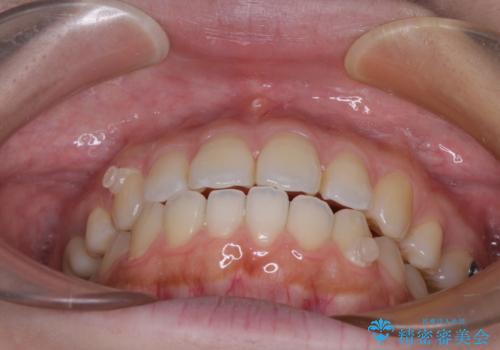

再矯正 開咬に後戻りした歯列をインビザラインで改善

デコボコと上下前歯の隙間が気になるものの、しっかりと治療をしたいという意思はないとのことで、インビザラインの中でもアライナー数に制約のあるライトパッケージを用いて、治療できる範囲まで歯列を改善していくこととしました。

インビザラインは前歯部の開咬に効果的であることが多く、ライトパッケージにもかかわらず、十分満足のいく仕上がりとなりました。